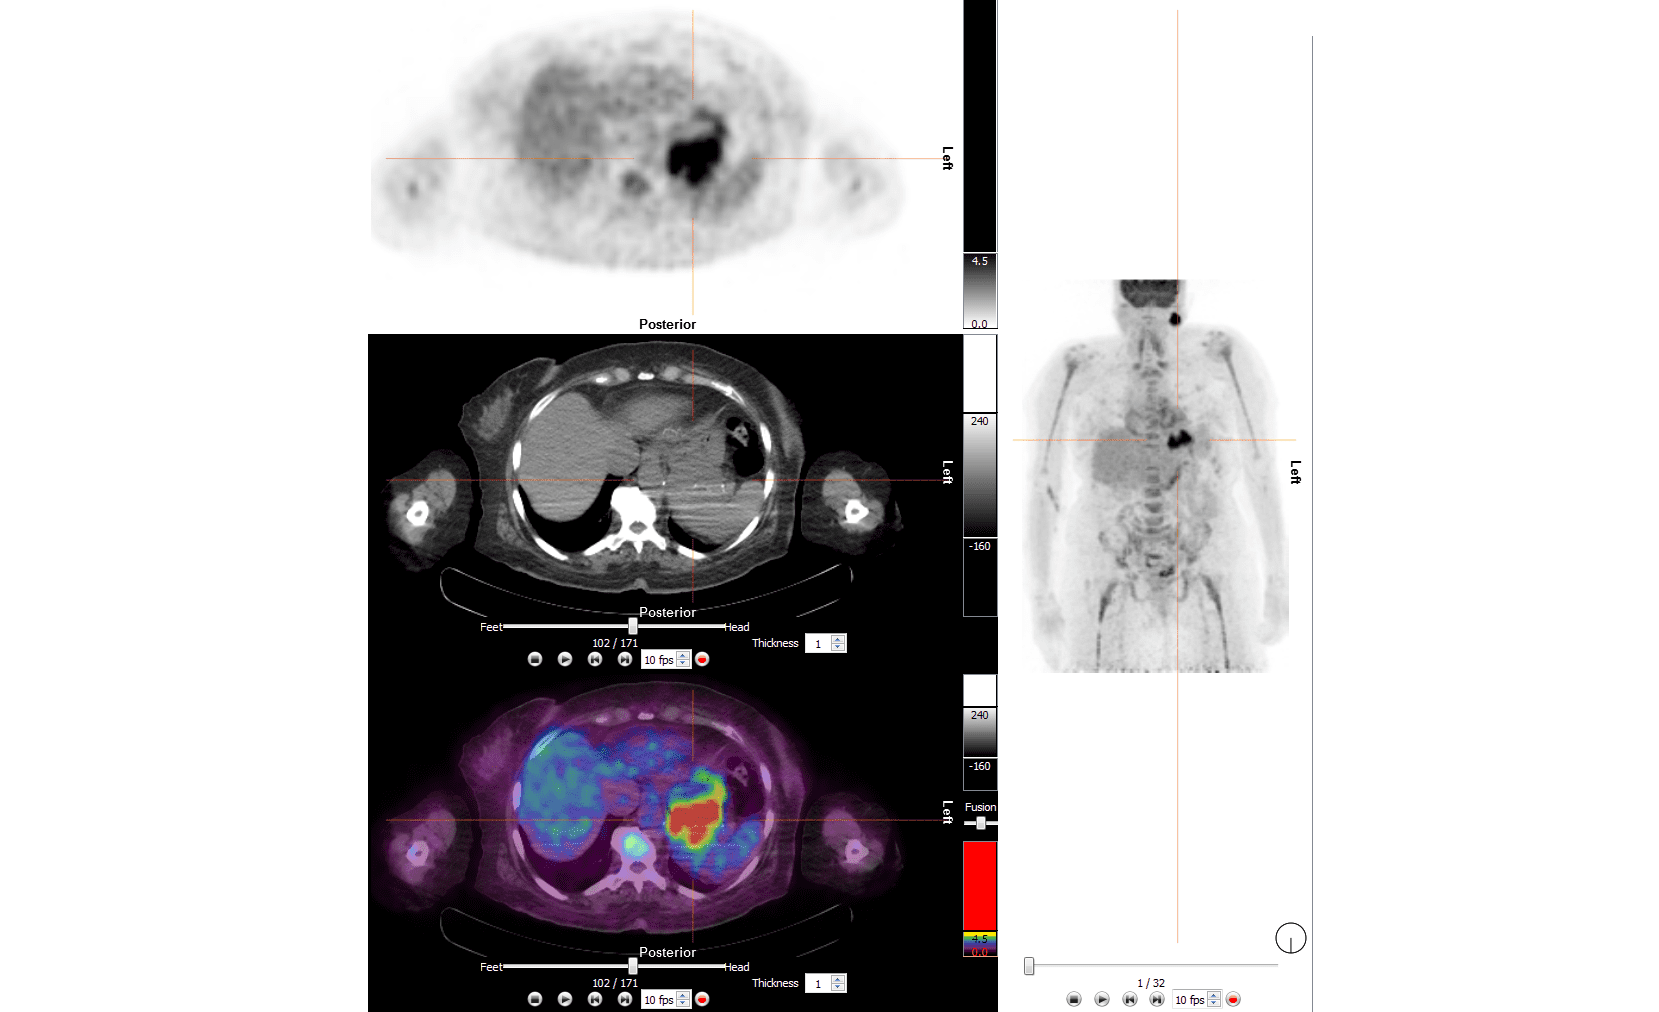

Moses Campus, along with Children’s Hospital at Montefiore Einstein, features 726 adult inpatient beds and 106 pediatric inpatient beds. The facility also offers services to outpatients. As an NCI-Designated Cancer Center, Moses provides diagnostic and therapeutic modalities through an active theranostics program. While training at Moses, residents partake in a particularly rigorous program in oncologic and non-oncologic pediatric and adult nuclear medicine. Our Transplant Center, also on-site, affords residents the ability to evaluate organ physiology pre- and post-transplant.